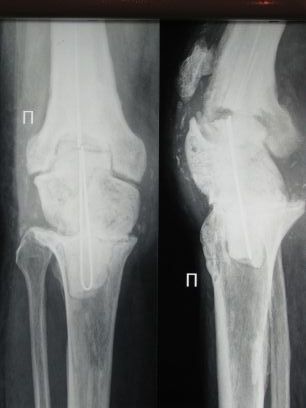

Пациент 69 лет.С 2002 года пережил три эндопротеза правого коленного

сустава. В ноябре 2008 года эндопротез удален, дефект заполнен

спейсером. В ноябре же был эпизод воспаления в области надколенника.

Задача на момент поступления - создать опорную ногу за короткий промежуток времени.